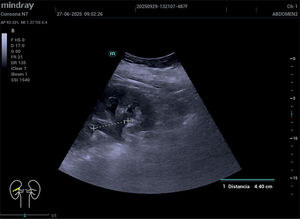

Cuando el cólico renal sigue doliendo, ¿entonces qué?